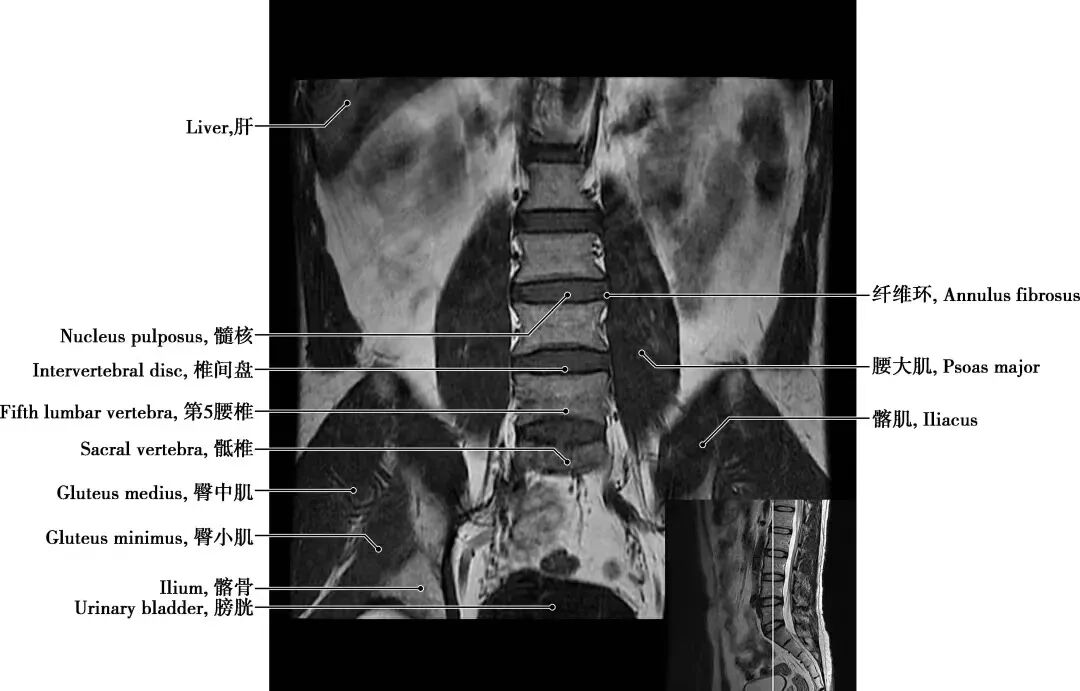

三、核磁共振(MRI):这是一种利用强磁场和射频信号的高级检查方法。

优点:磁共振检查在软组织成像上更胜于腰椎CT。可以很好地观察腰椎间盘的情况,更清晰地显示椎间盘的形态及其与硬膜囊、神经根等周围组织的关系。在脊髓病变、炎性病变、出血性病变及腰部肌肉病变等方面也具有优势。此外,磁共振检查不存在X线辐射,是较为安全可靠的检查。